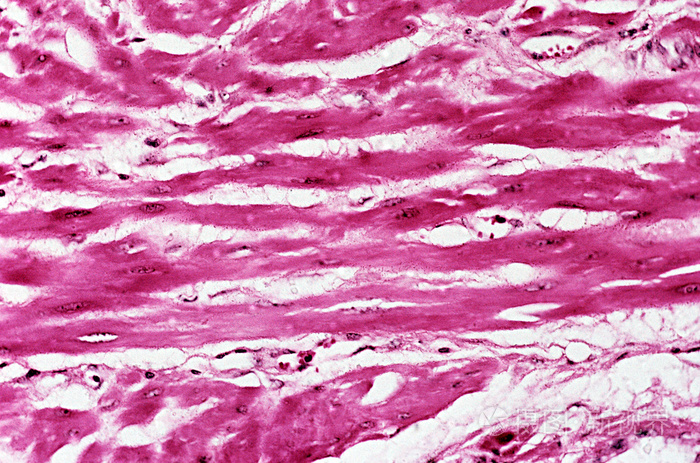

图-4:部分粘膜肌层被肿瘤细胞破坏.